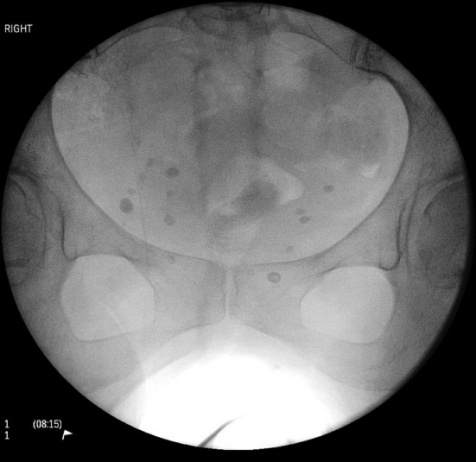

由于对侧髋关节与手术侧影像重叠,可能导致成像判读困难。此外,既存的对侧植入物可能进一步干扰影像学评估。通过仔细比对股骨头尺寸差异(图21与图22),可有效实现鉴别诊断。

什么是c型臂术中透视骨科精读 | 股骨近端骨折的转子区域与矢状面力线术中透视技巧_https://www.jmylbn.com_新闻资讯_第21张

图21

什么是c型臂术中透视骨科精读 | 股骨近端骨折的转子区域与矢状面力线术中透视技巧_https://www.jmylbn.com_新闻资讯_第22张

图22

如下方术中影像所示,最靠近影像增强器(距射线发射源最远)的股骨头显像较小且包含植入物。相反,距离射线发射源最近的股骨头显像尺寸显著增大(图23)。

什么是c型臂术中透视骨科精读 | 股骨近端骨折的转子区域与矢状面力线术中透视技巧_https://www.jmylbn.com_新闻资讯_第23张

图23